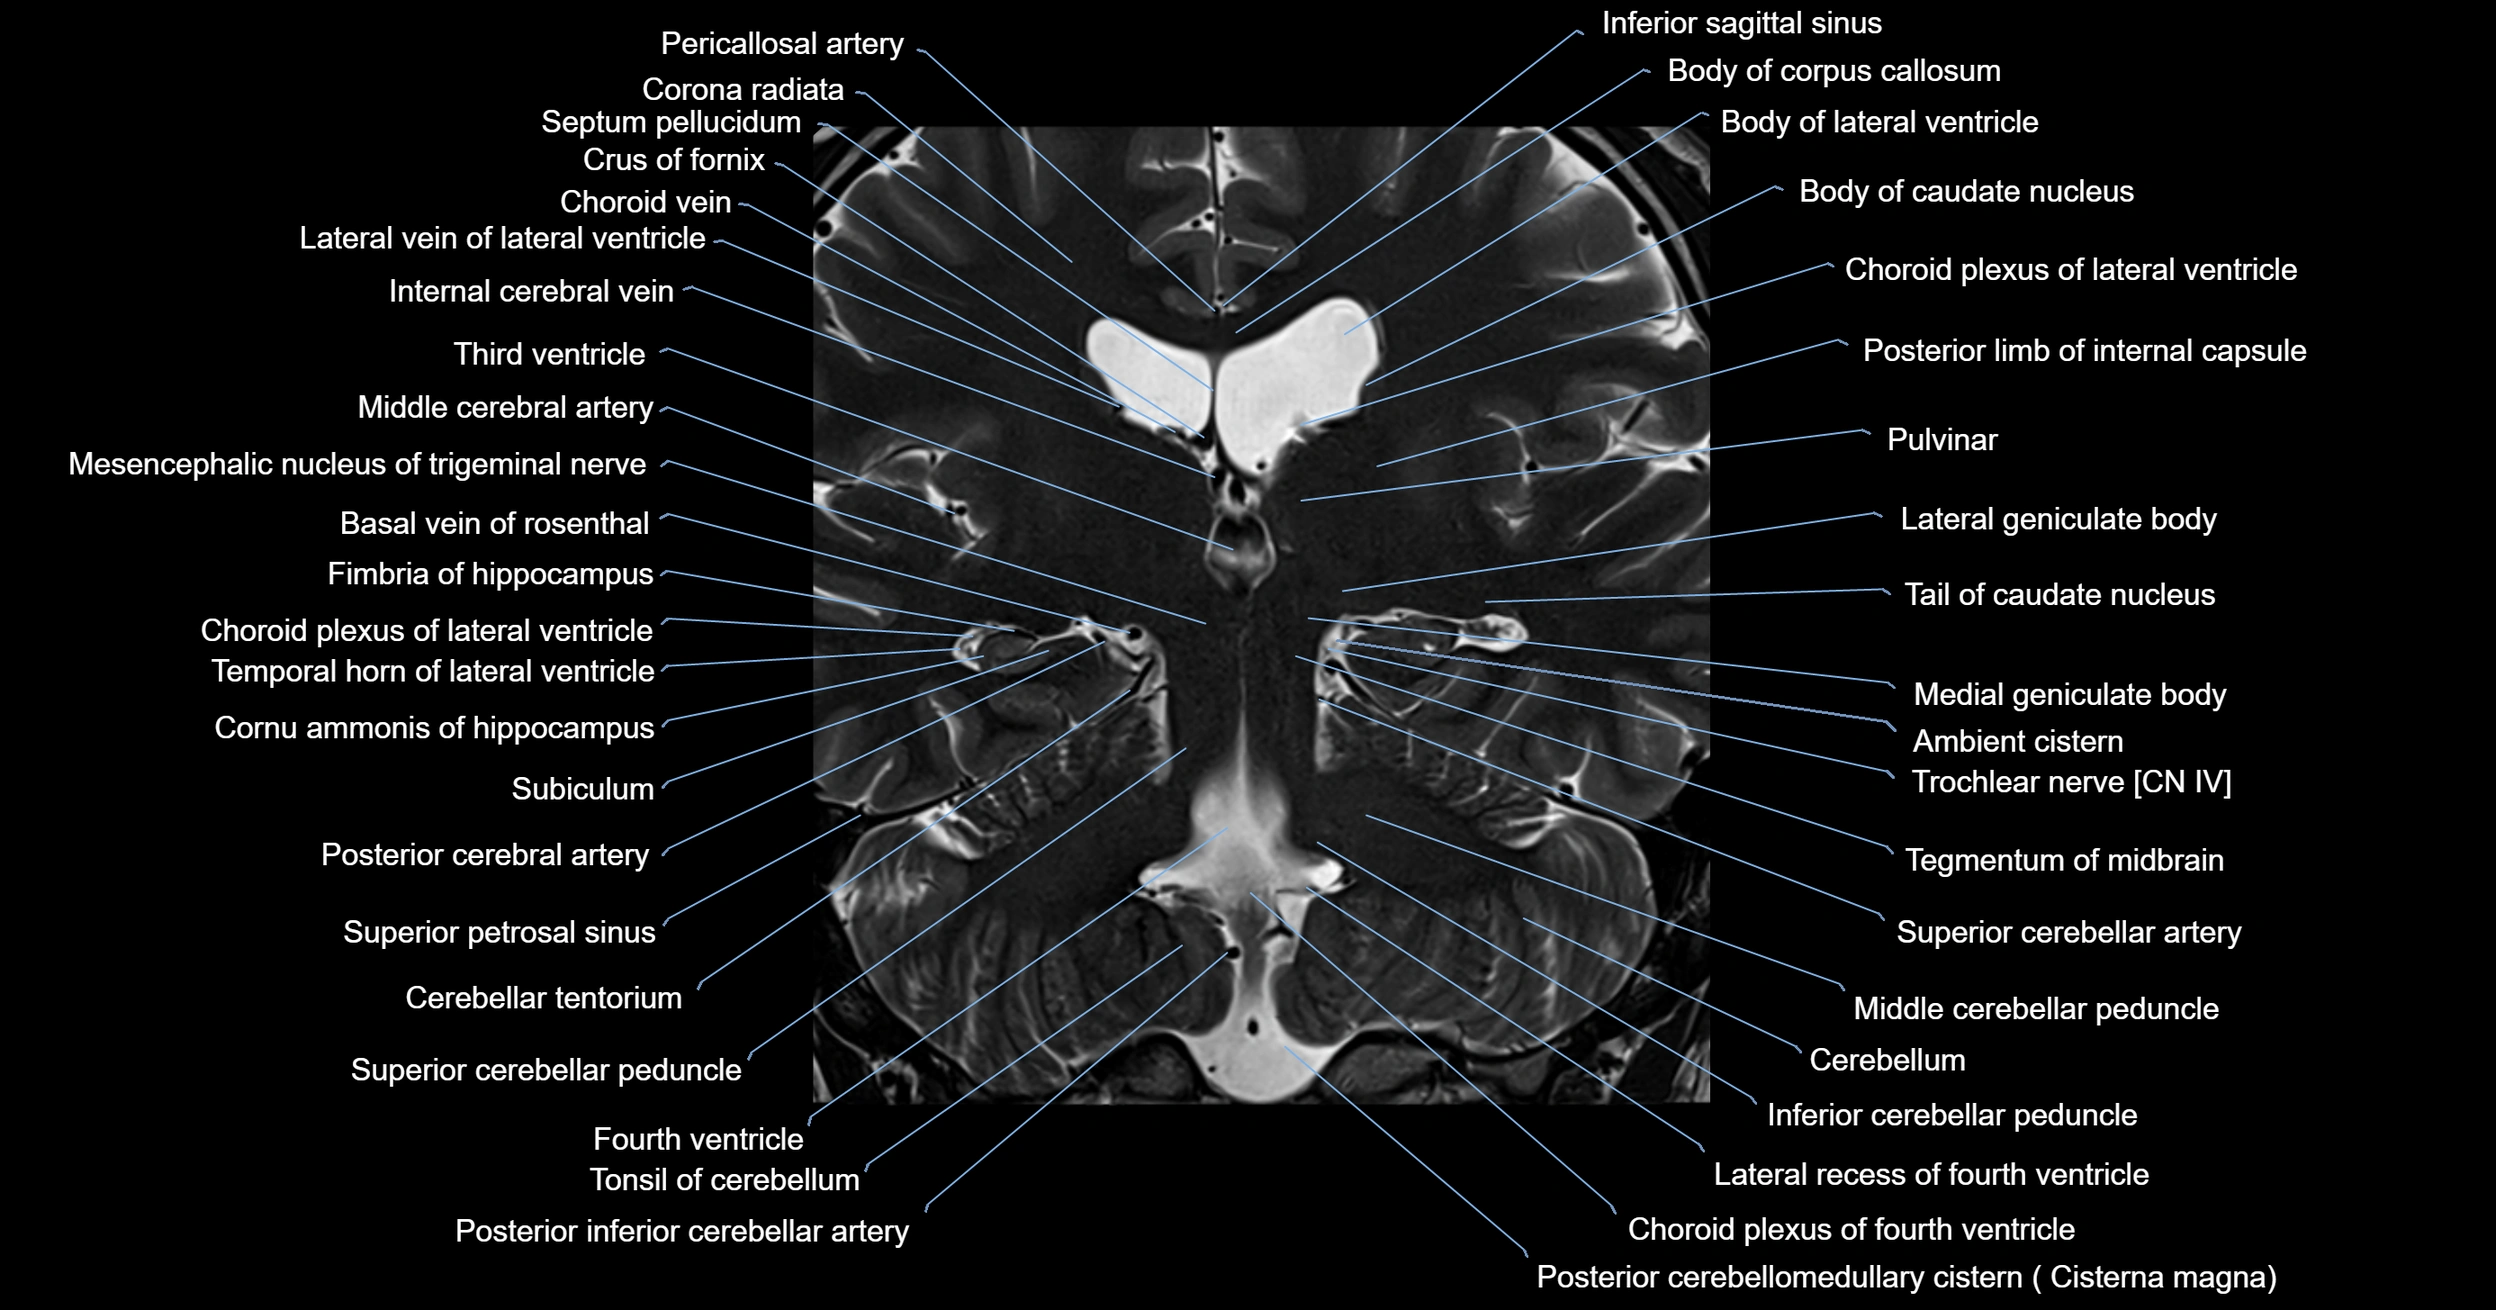

- Ambient cistern

- Basal vein of rosenthal

- Cerebellar tentorium

- Cerebellum

- Choroid plexus of fourth ventricle

- Choroid plexus of the lateral ventricle

- Fourth ventricle

- Inferior cerebellar peduncle

- Inferior sagittal sinus

- Lateral geniculate body

- Medial geniculate body

- Middle cerebellar peduncle

- Posterior cerebellomedullary cistern (cisterna magna)

- Posterior inferior cerebellar artery

- Pulvinar

- Superior cerebellar peduncle

- Superior petrosal sinus

- Tail of caudate nucleus

- Tegmentum of midbrain

- Temporal horn of lateral ventricle

- Tonsil of cerebellum

- Trochlear nerve (Cranial nerve IV)